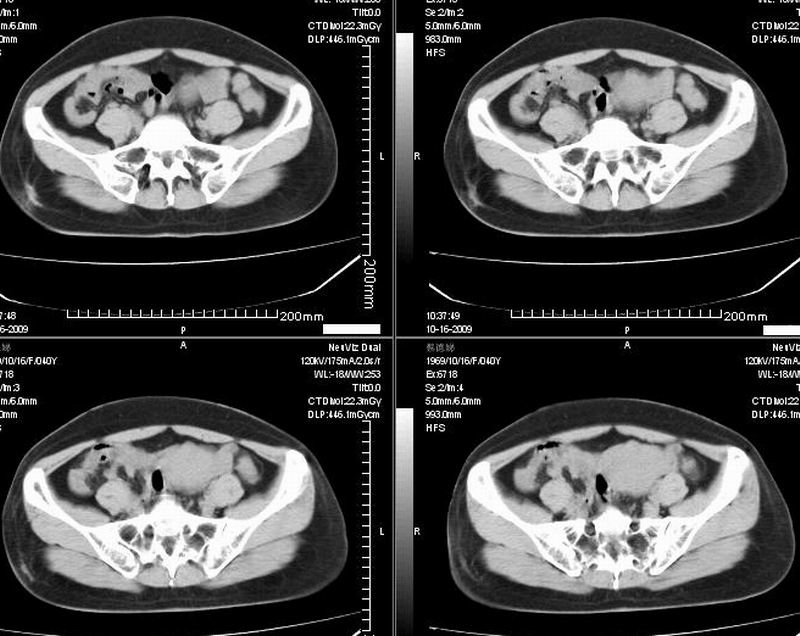

女:40y:下腹隐痛1周+,无其它不适,这个子宫会太一点吗?有临床意义吗?

宫腔内有积液,考虑炎症可能

子宫偏左,略显增大,期内可见低密度改变,考虑宫腔积液可能。

子宫偏左,略显增大,期内可见低密度改变,考虑宫腔积液可能。 不能除外肌瘤可能。

子宫体积稍增大,其内见低密度影。考虑宫腔积液可能。

子宫不规则的增大 宫腔内积液 有多种考虑

1 子宫肌瘤

2 子宫腺肌症

3 子宫内膜炎

4 月经期 (宫腔内积血)